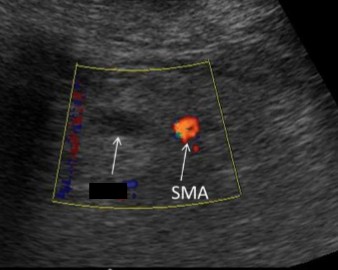

Where does the superior mesenteric vein lie in relation to the superior mesenteric artery?

To the right

What is the name of the vessel crossed out and to the right of the SMA?

Superior mesenteric vein